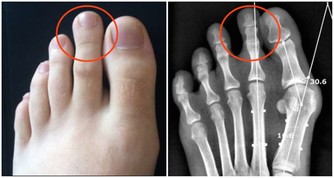

Q:缺乏鈣質會使身體肌肉緊繃?

人體缺乏鈣質時,其實害怕的是血液含鈣量不足,以致於影響身體機能,醫學上稱為低血鈣症,它從神經的傳導訊息到內分泌,甚至是肌肉收縮都有關係。通常低血鈣症會影響三種肌肉:

骨骼肌:缺鈣會讓人肌肉緊繃,無法放鬆。

平滑肌:缺鈣時心臟會亂跳,反而會心律不整,有時可會導致猝死問題。

心肌:與腸胃道的蠕動跟吸收及血管有關,會影響血管收縮。